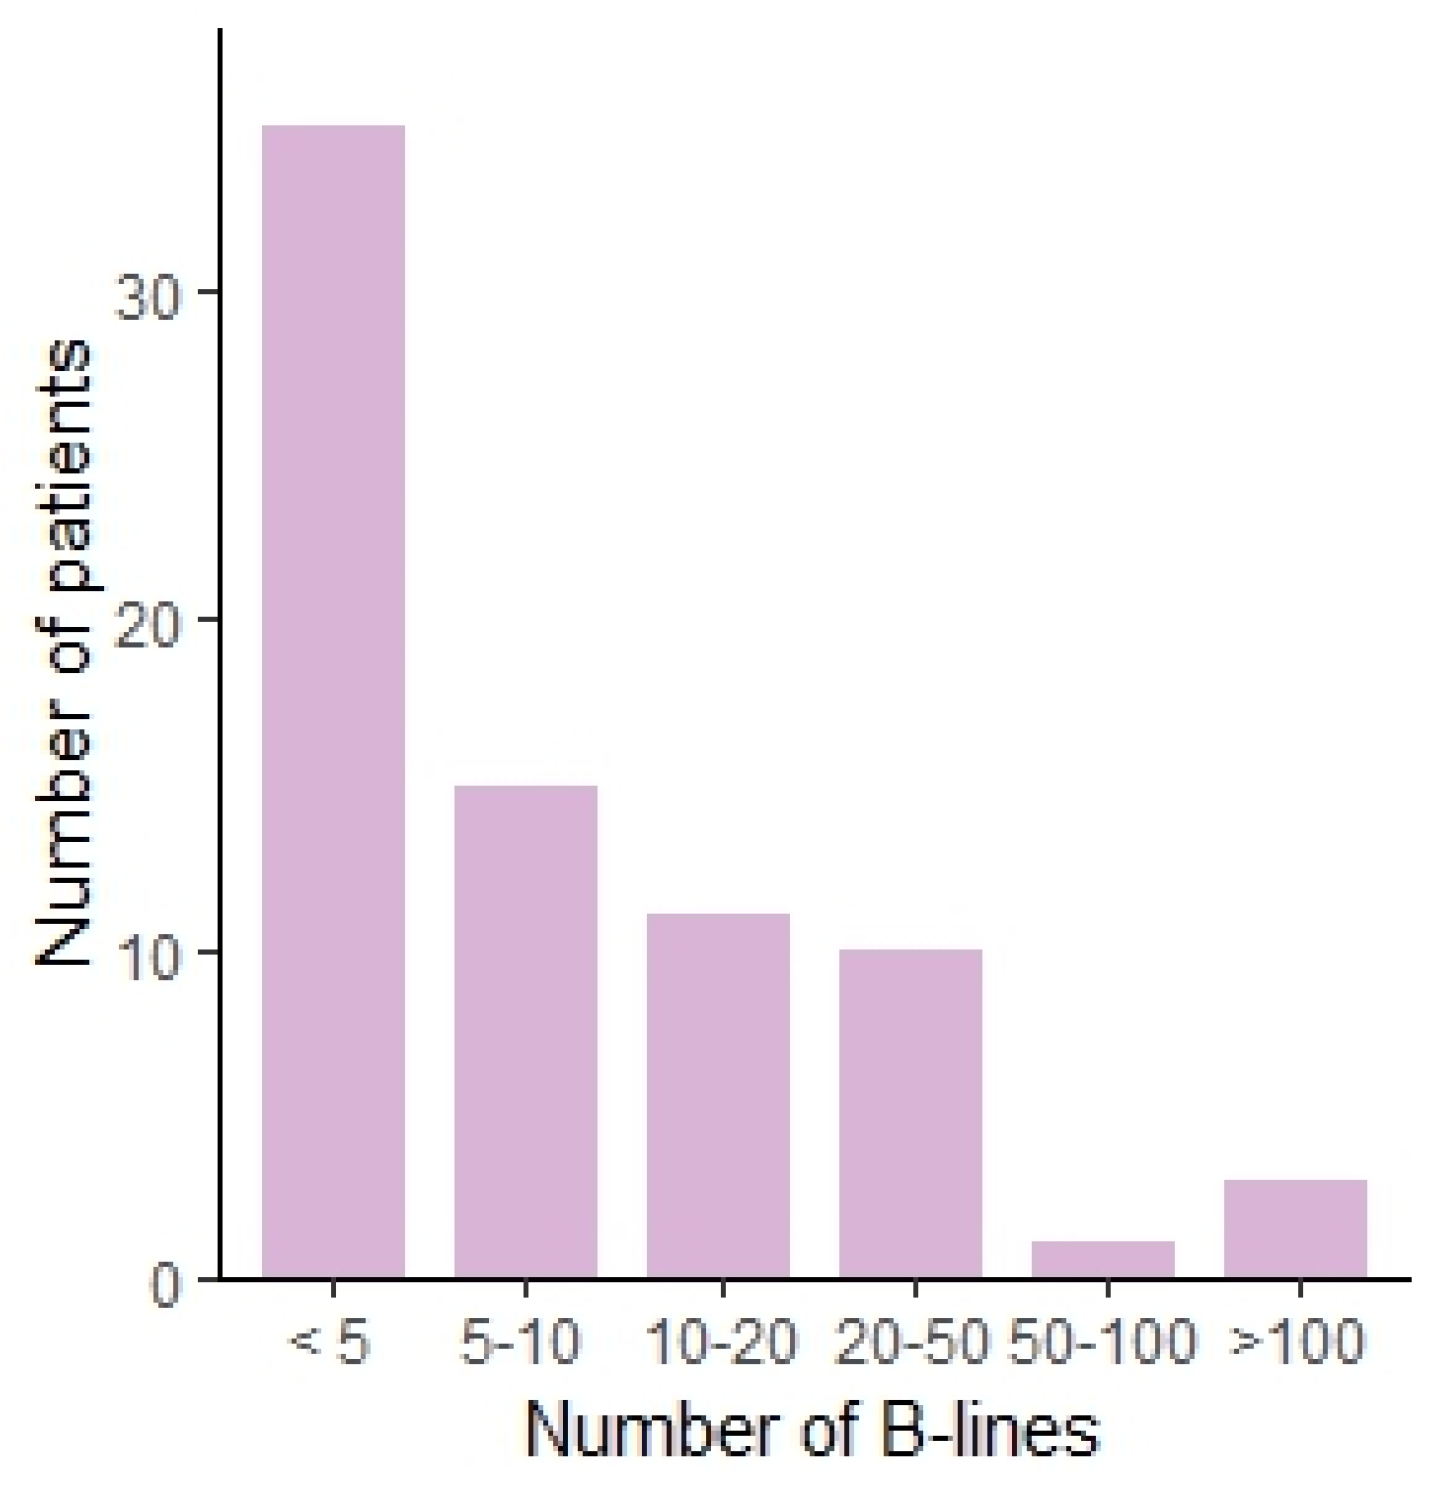

| B-lines | |

| <5 | 35 (46.7%) |

| 5–10 | 15 (20%) |

| 10–20 | 11 (14.6%) |

| 20–50 | 10 (13.3%) |

| 50–100 | 1 (1.3%) |

| >100 | 3 (4%) |